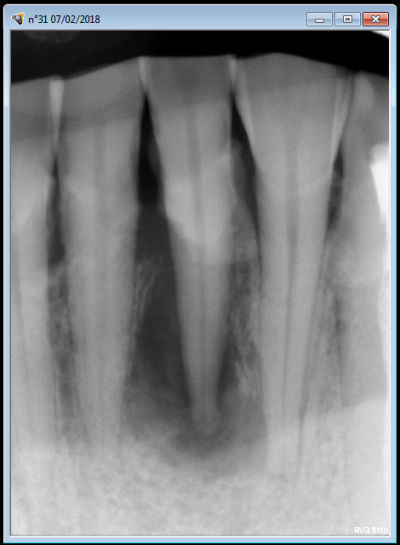

" j'ai deux dents mobiles sur deux patients différents chez qui, je pense, l'extraction-implantation pourrait se tenter... Pourriez-vous me donner votre avis ?

Autre cas, cette 31. Là, c'est peut être un peu extrême non ? Là c'est pareil ? Aucune contention ? faire une contention avec 32 41 mais sécuriserait j'avoue... Qu'en pensez-vous ?

Par contre ta 31, ç est nickel , tu fais l endo avant et hop tu racles ce qui depasse .pas besoin de mettre quoi que ce soit au bout .

31 mobile kymblw - Eugenol

ouaip ,ç est quand meme bien de supprimer la cause initiale avant toute chose , hein .

pour ta 31 il y a de fortes usures des bords libres . cela fait pense à 1 perte de calage post avec style usure des canines du bas avec un gros méplat .

ce qui veut dire que si tu ne comptes pas la raser , il faut au moins la mettre en sous occ .

mais attention ,il faut la mettre en sous occ ,y compris pendant les trajets de para-fonction .

si tu n'es pas sur de ton coup , ou si par manque de calage post , elle touche tjs ,alors oui ,il vaut mieux faire un petit calage par compo lors de la réimplantation .

lorsque tu fais l'endo tu peux faire une para apicale , mais lorsque tu feras l'extraction réimplantation ,il te faudra faire obligatoirement une anesthésie intraligamentaire ( même si tu as déjà fait une para apicale ).

l'intraligue , t'aidera à extraire sans forcer d'une part , mais surtout commencera à pré-décoller les parties molles de l'os par le jeu de la pression .

ç est un cas tranquille , ça ! t'en profiteras pour bien la detartrer aussi :-)